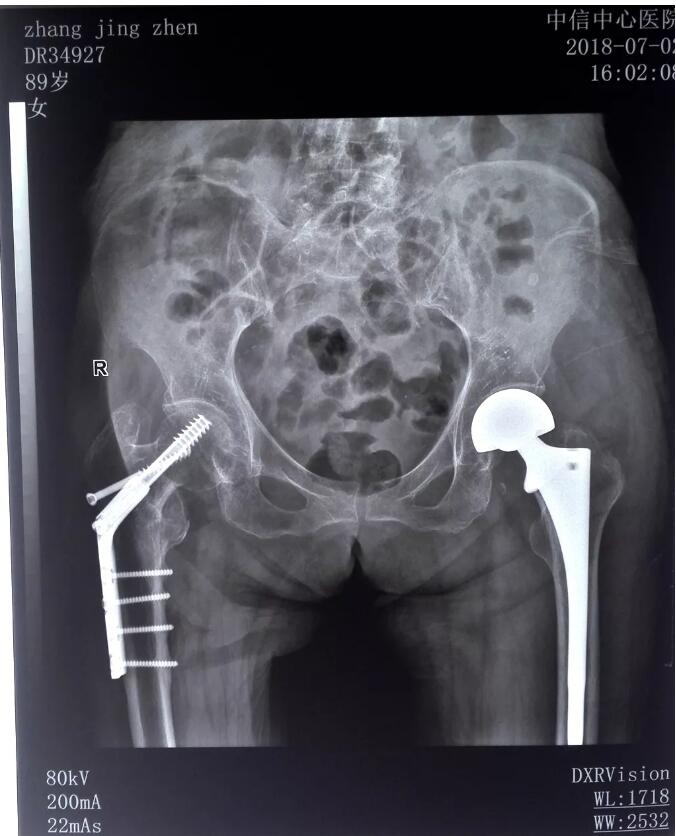

現(xiàn)年89歲的張靜珍老人,因不慎摔倒導(dǎo)致右髖部疼痛、站立受限、無法正常行走。就近急診到我院診治,X光拍片檢查顯示,右髖關(guān)節(jié)股骨頸骨皮質(zhì)不連續(xù),股骨頸骨折,并入住我院骨科治療。由于患者年事已高,對(duì)麻醉與手術(shù)的耐受性差,風(fēng)險(xiǎn)性極高。骨科主任柳順偉立即組織科室技術(shù)骨干會(huì)診、討論,很快為其制定了最佳的手術(shù)方案,精心做好各項(xiàng)術(shù)前準(zhǔn)備工作。在內(nèi)科、麻醉科等多科支持下,骨科主任柳順偉、主治醫(yī)師毛萬青、住院醫(yī)師宋羅明共同為其實(shí)施了“右股骨頸骨折人工股骨頭置換術(shù)”,整臺(tái)手術(shù)歷時(shí)90分鐘獲得圓滿成功。該手術(shù)的成功實(shí)施,再次彰顯了我院治療高齡骨折的救治實(shí)力,也體現(xiàn)出我院髖關(guān)節(jié)置換術(shù)單病種質(zhì)量管理工作的規(guī)范有序。

術(shù)后x光片

俗話說“傷筋動(dòng)骨一百天!币馑际钦f,如果骨頭傷著了,會(huì)要很長的時(shí)間才能康復(fù)。術(shù)后,通過使用路徑管理及康復(fù)指導(dǎo)訓(xùn)練,老人很快就能扶著助行器行走了。對(duì)于手術(shù)效果和醫(yī)院服務(wù),老人贊不絕口,并對(duì)我院骨科醫(yī)護(hù)人員的高尚的醫(yī)德、高超的醫(yī)術(shù)和高度負(fù)責(zé)的態(tài)度深表感謝。